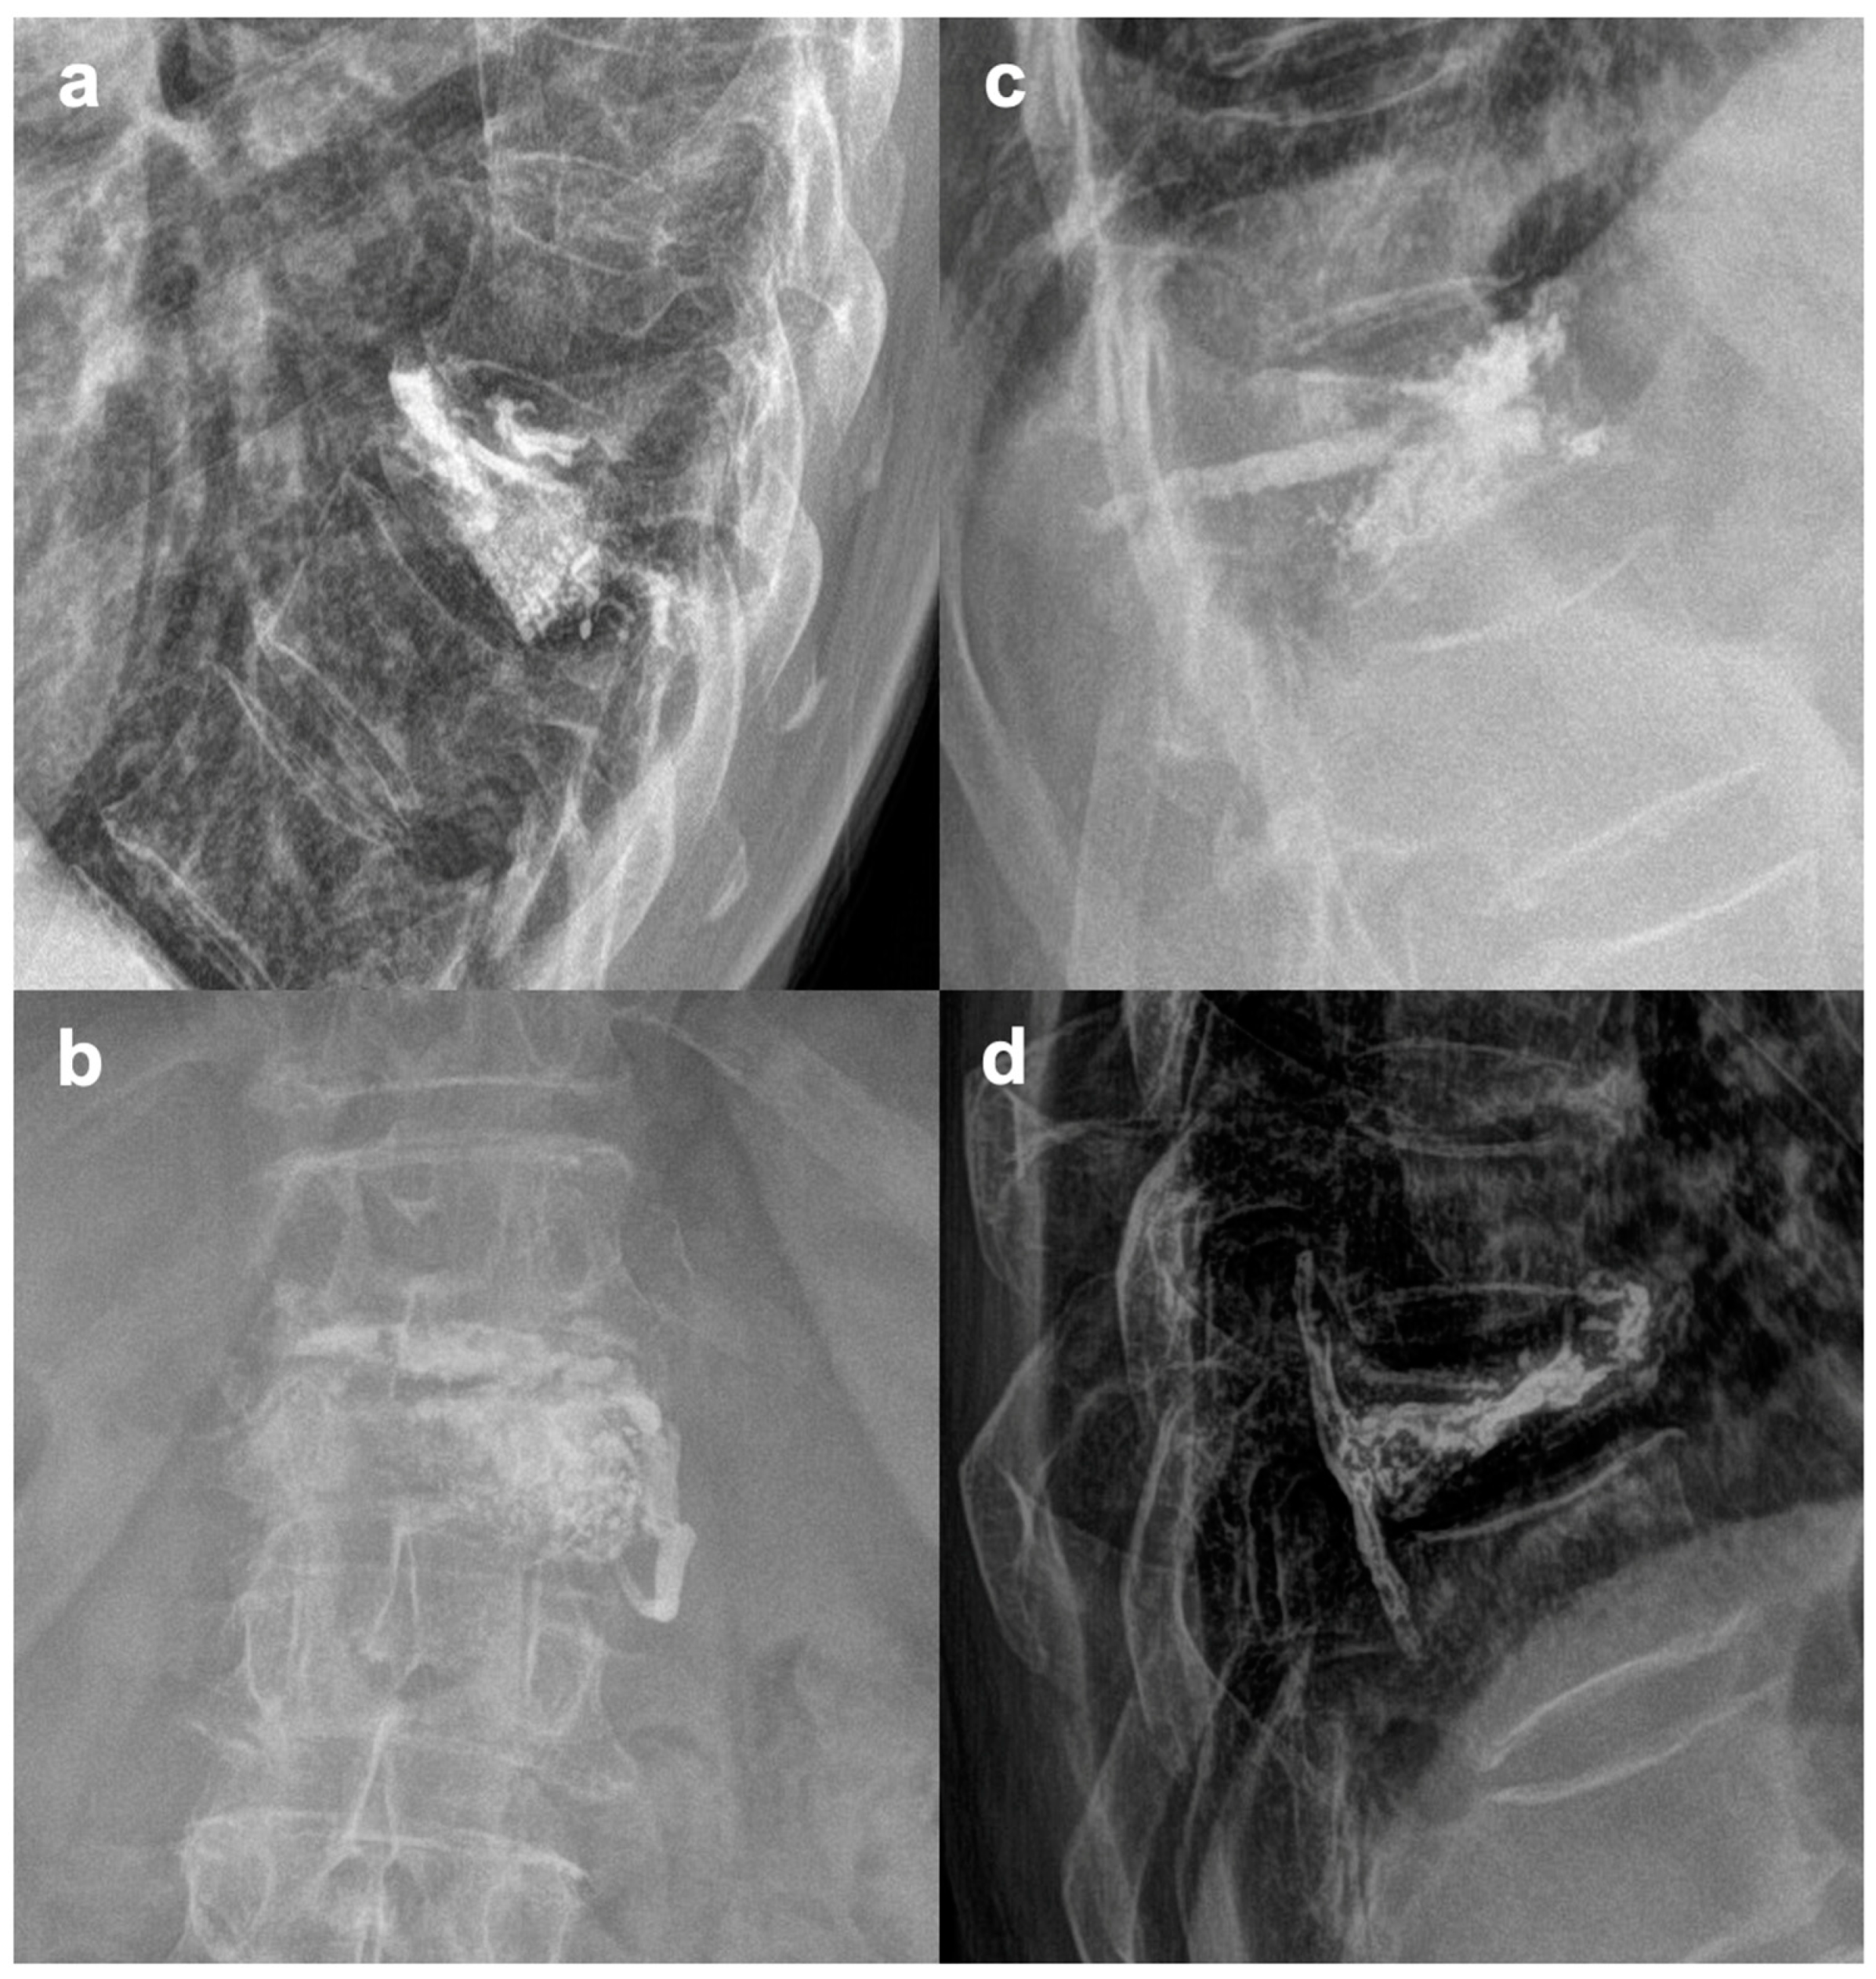

2.2. Surgical Technique